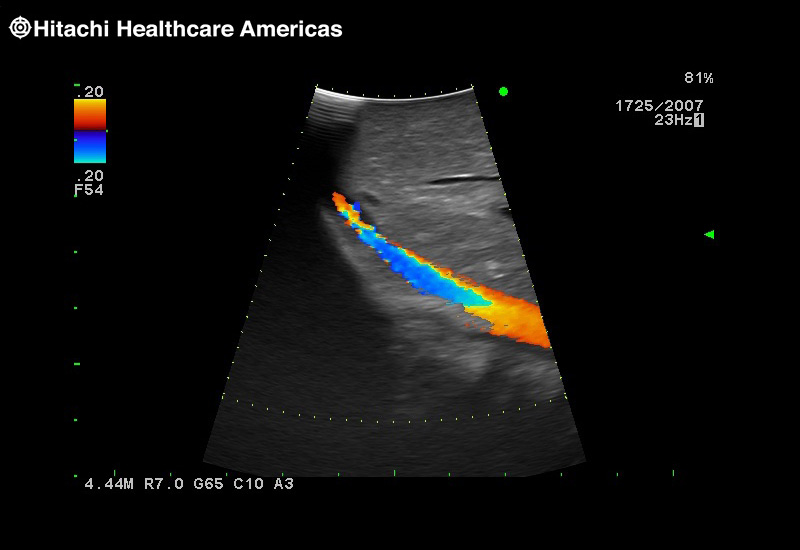

Superior guidance for all applications

Fujifilm Healthcare Americas is committed to designing tools that help surgeons navigate inside the human body and provide the necessary information to immediately make critical surgical decisions.

Fujifilm Healthcare's dedication to Surgeons provides outstanding ultrasound technology, professional support and the specialized tools necessary to best perform comprehensive real-time ultrasound imaging in Breast Surgery, General Surgery, Laparoscopic Surgery, Neurosurgery, Robotic Surgery and Surgical Oncology.

Giving the surgeon complete control

The Fujifilm Healthcare transducer utilizes the full benefits of the Wrist Articulation™ of the robotic instruments to capture real-time ultrasound imaging even at complex angles and difficult-to-reach areas.

A critical function of robotic ultrasound guidance is tumor margin identification. Fujifilm's family of robotic probes all have the optimum location of the attaching mechanism that allows for full wrist articulation of the probe. The result is an increased confidence that the tumor margins have been completely identified.

Imaging Clearly Defined

State-of-the-art digital architecture and advanced imaging features to redefine the capabilities of surgical ultrasound.